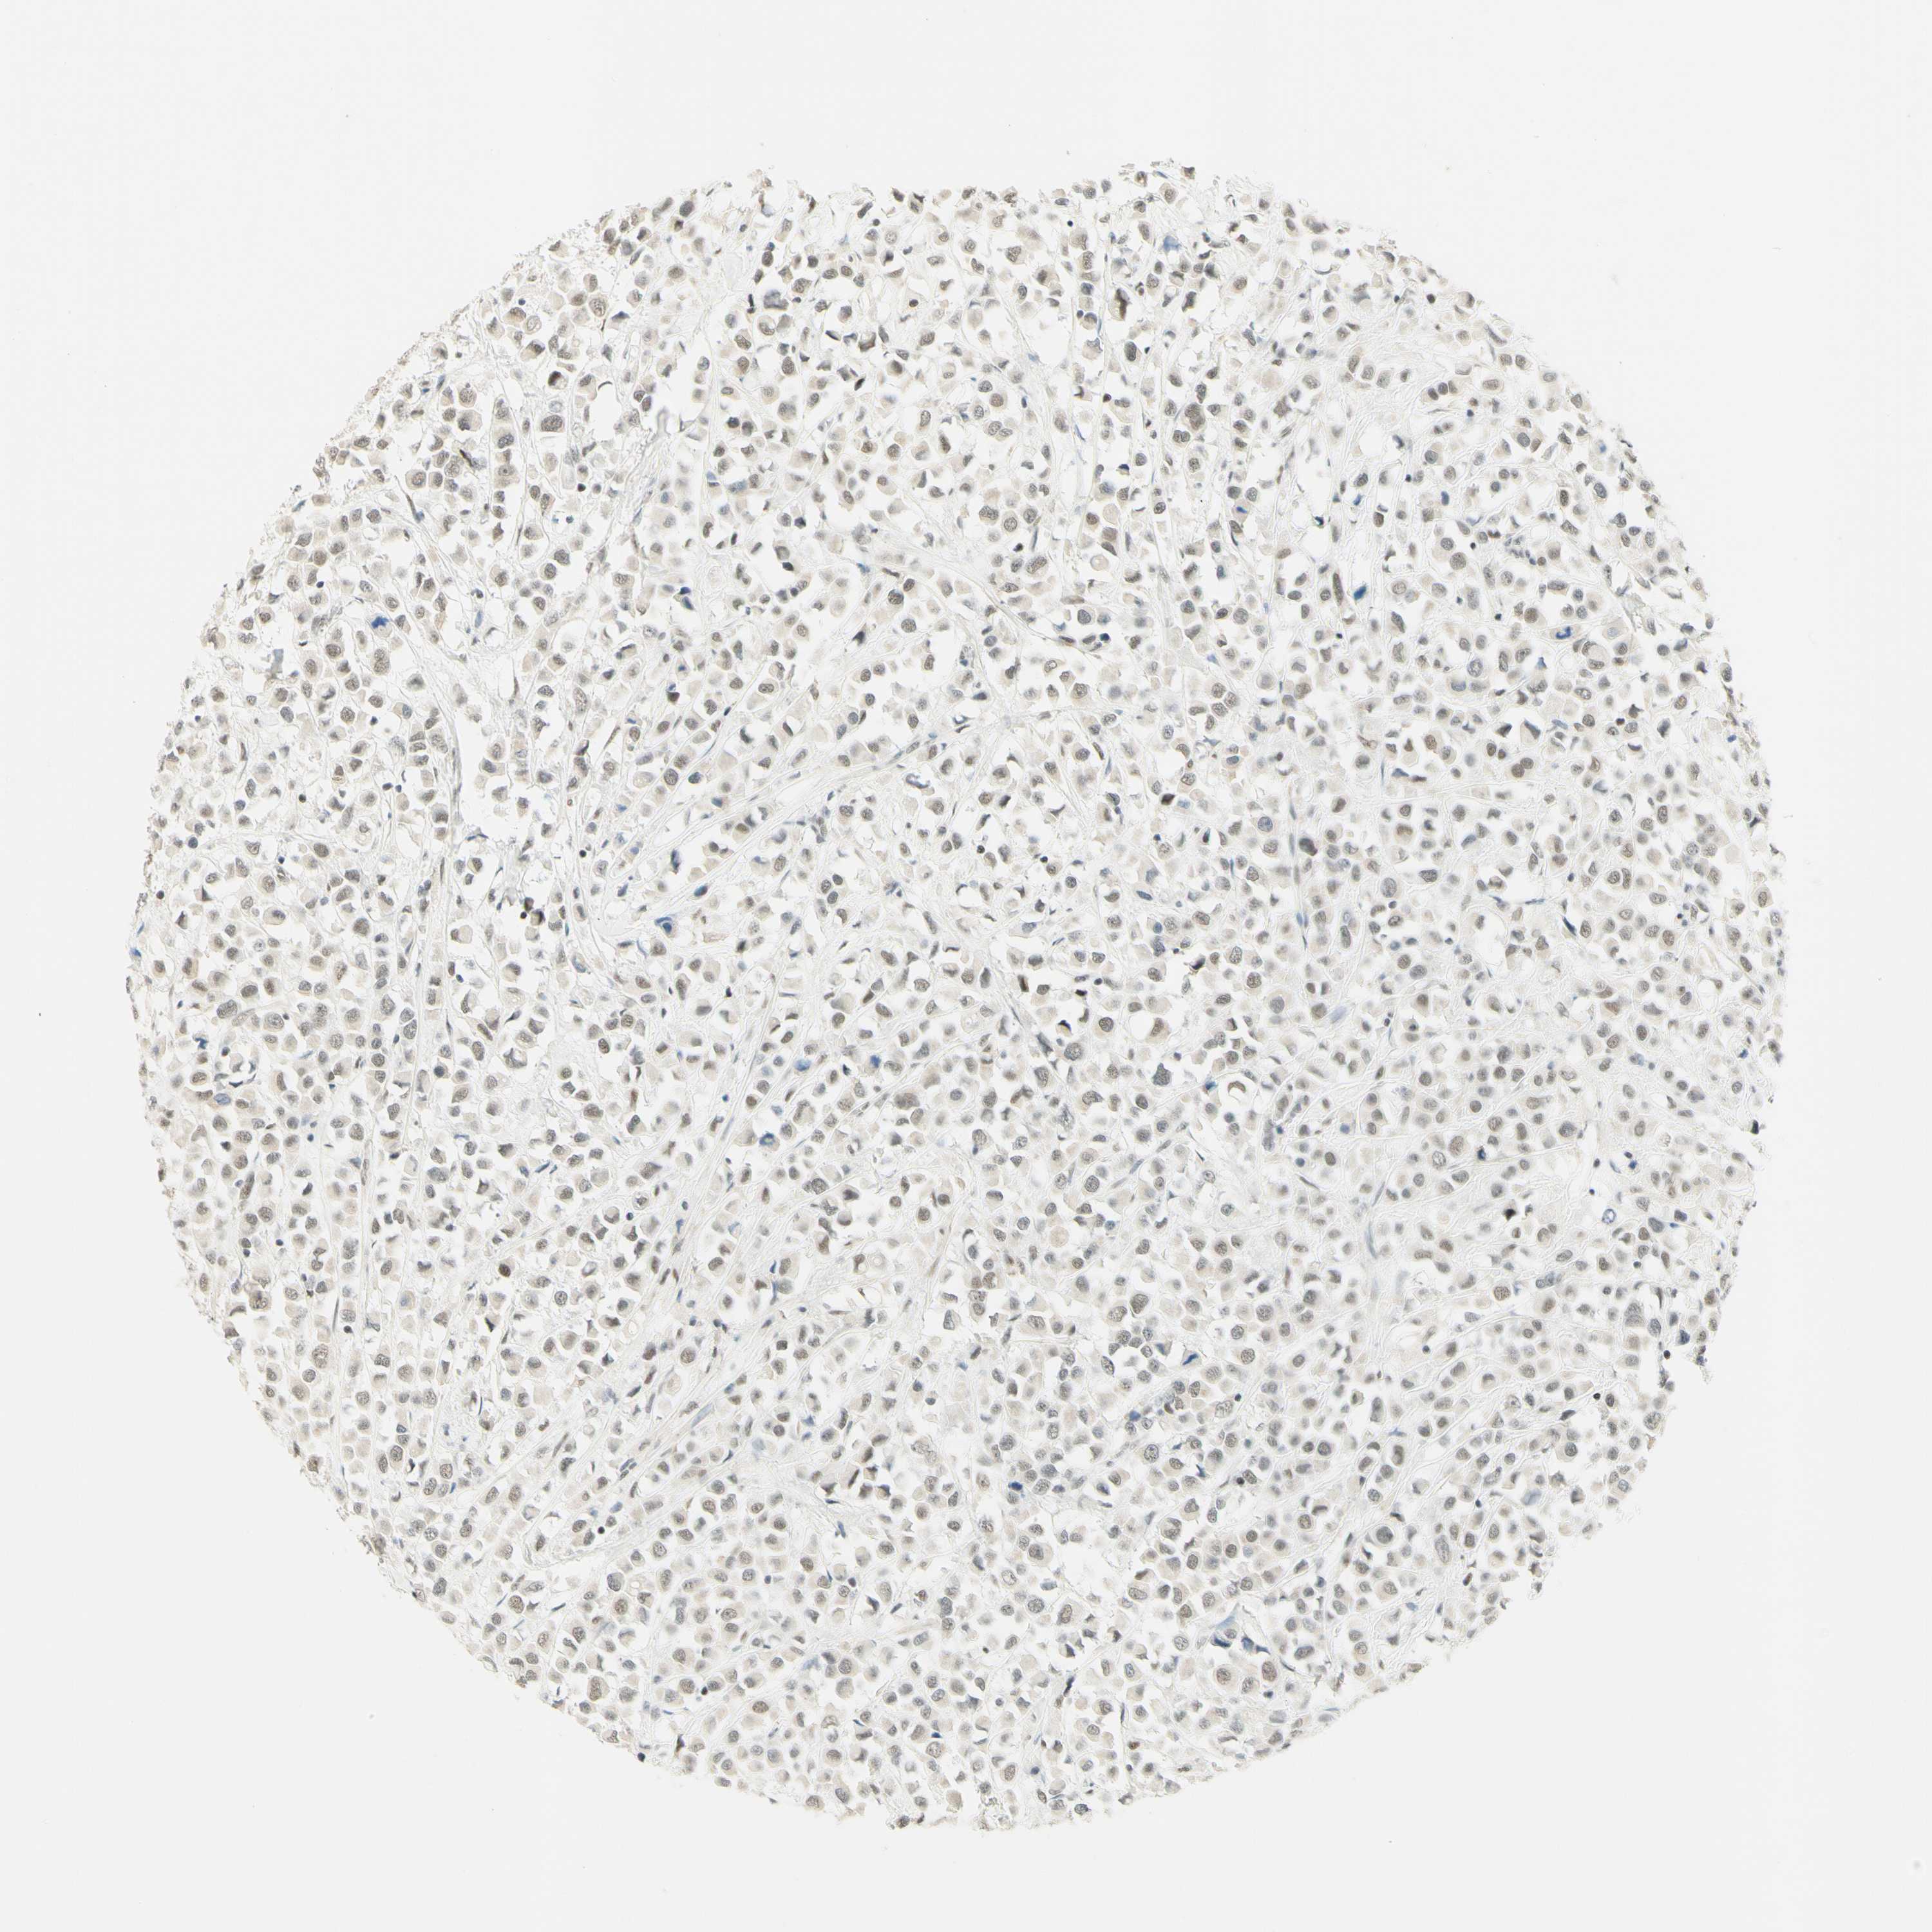

CANCER BREAST CANCER Show tissue menu

BRCA TCGA BRCA VALIDATION PROTEIN EXPRESSION

ANTIBODIES

AND

VALIDATION